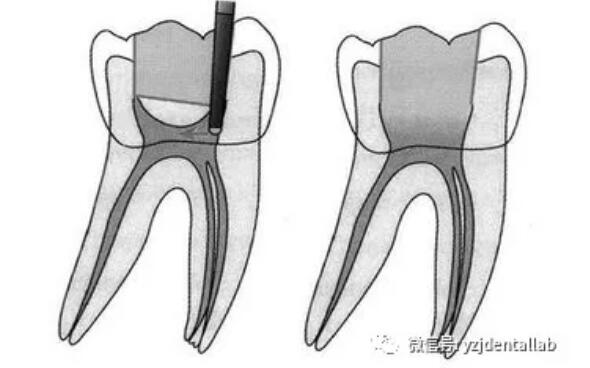

、開(kāi)髓去腐質(zhì)

去凈腐質(zhì)和原有充填物、揭凈隨頂,看到整個(gè)髓底解剖結(jié)構(gòu)、髓壁與根管壁連續(xù)流暢、沒(méi)有牙頸部臺(tái)階,沒(méi)有過(guò)度切割髓壁和髓底以便后續(xù)治療順利進(jìn)行。

開(kāi)髓步驟:

局麻--上橡皮障--去除所有腐質(zhì)--接髓頂--形成與根尖孔1/3的直線(xiàn)。